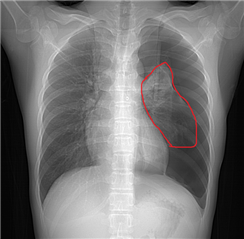

1.X线:可以能发现肺部有没有气胸,肺压迫的程度。

X线:红色画线代表被压缩的肺 胸部CT:左肺黑色部分是气体